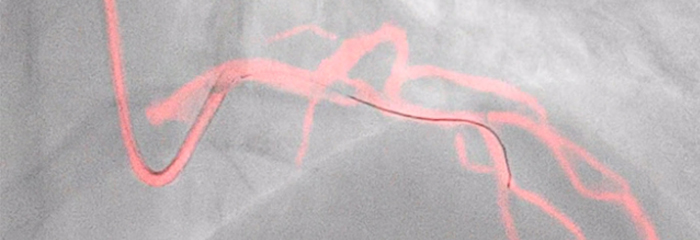

Для все большего числа пациентов с ИБС выбирается минимально инвазивное лечение, однако в этом случае оптимальному планированию лечения препятствует тот факт, что для коронарной ангиографии в режиме 2D существуют ограничения по обнаружению и оценке коронарного стеноза. Данные, получаемые до и во время процедуры, не объединяются согласованно и надлежащим образом, что увеличивает время лечения и усложняет его планирование. Разработанные нами решения для кардиологических исследований устраняют эти проблемы, чтобы вы могли реализовать преимущества клинической эффективности в своей рентгеноперационной:

Ангиография, iFR, ВСУЗИ и мониторинг гемодинамических параметров, а также предварительное планирование кардиологических интервенций и экспертные приложения интегрированы в единый интерфейс ангиографической системы, что обеспечивает просмотр, управление и настройку конфигурации на мониторе с помощью одного контроллера у стола или из пультовой.